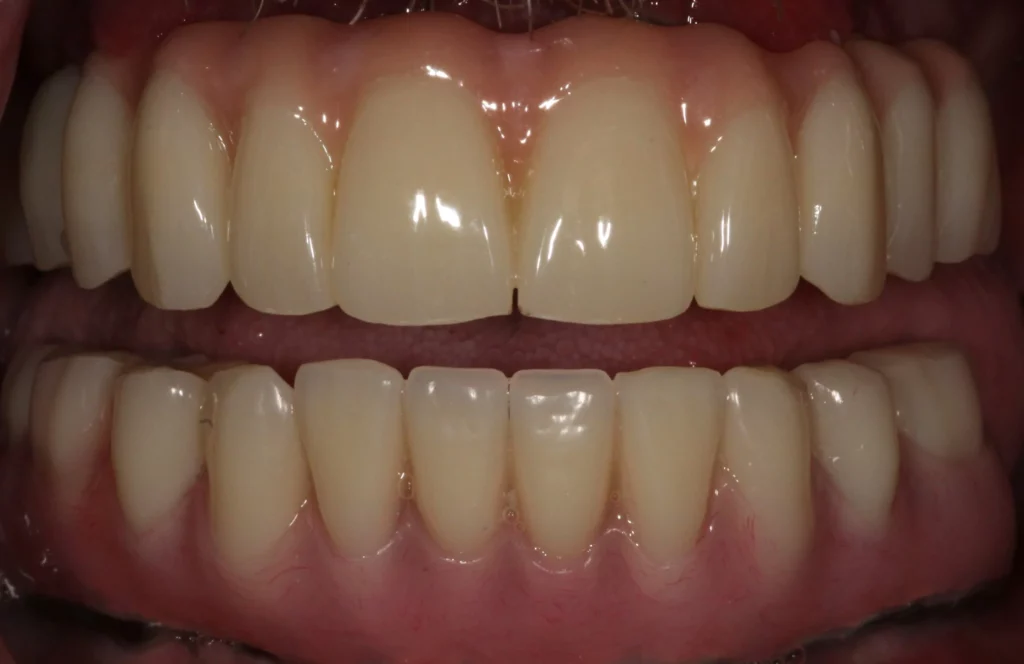

Note that you may not need a bridge if you simply need a single tooth dental implant. However, if a dental bridge is right for you, using state-of-the-art materials we can make dental bridges feel and look completely natural.

A Fixed Implant Bridge is a good option if you don’t want to change the good teeth around your missing tooth. You can see an example of this at the top of this page.